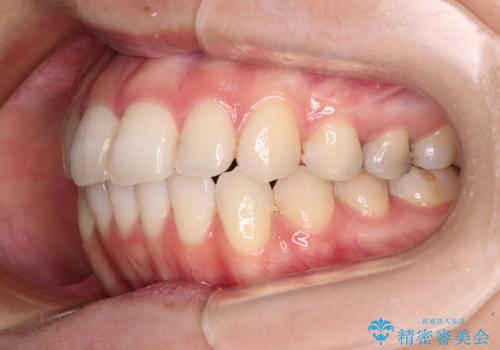

- 前歯のデコボコを気にして来院された患者様です。

主に下顎歯列全体の後方移動とIPR(歯と歯の間を削る)によってデコボコが解消するように設計し、インビザラインにより治療を行うこととしました。

舌突出癖がある方ですと、叢生が解消すると同時に前方に拡大されてしまいますが、ゴムかけをしっかりと行ってくださったこともあり、スッキリとした仕上がりとなりました。